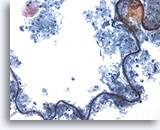

Las células vegetales en muestras respiratorias pueden imitar a las células epiteliales atípicas o incluso cáncer. 60x

Las células vegetales en muestras respiratorias pueden imitar a las células epiteliales atípicas o incluso cáncer.

60x